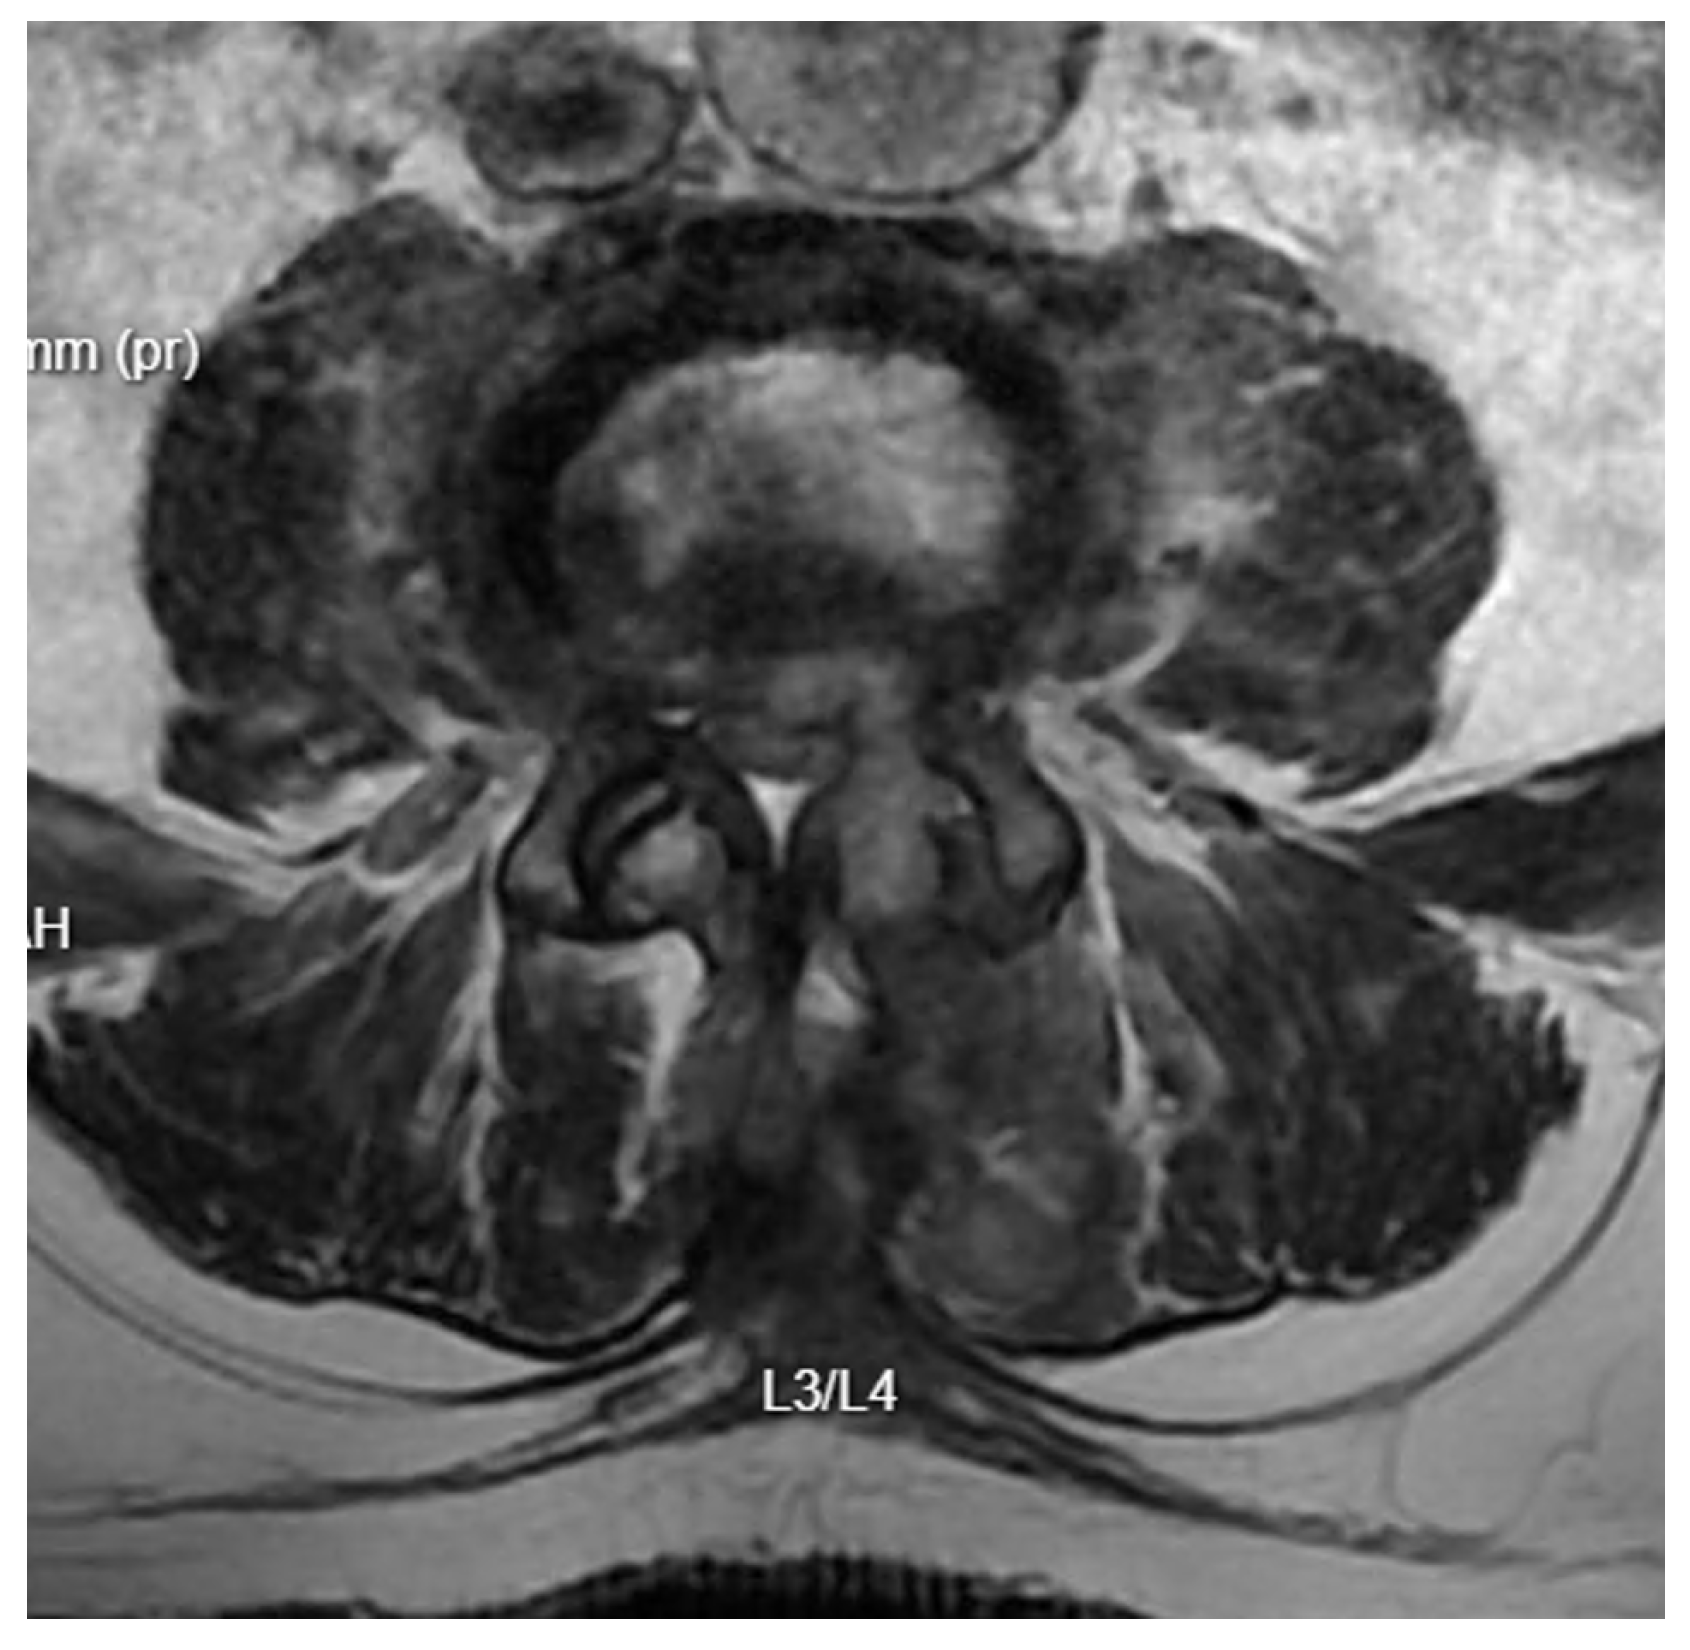

Diagnostic Evolution: After a week of conservative treatment without improvement, a follow-up MRI was ordered(Figure 3), which unambiguously identified spondylodiscitis with an abscess in the canal, causing compression of the dural sac and both S1 nerves (Figure 4). The patient’s pain syndrome worsened significantly, VAS 9 in the lower spine, leading to her qualification for surgical treatment.

Figure 4. Pre-operative T2 axial MRI image at the L5/S1 level one week after admission to the neurology department.